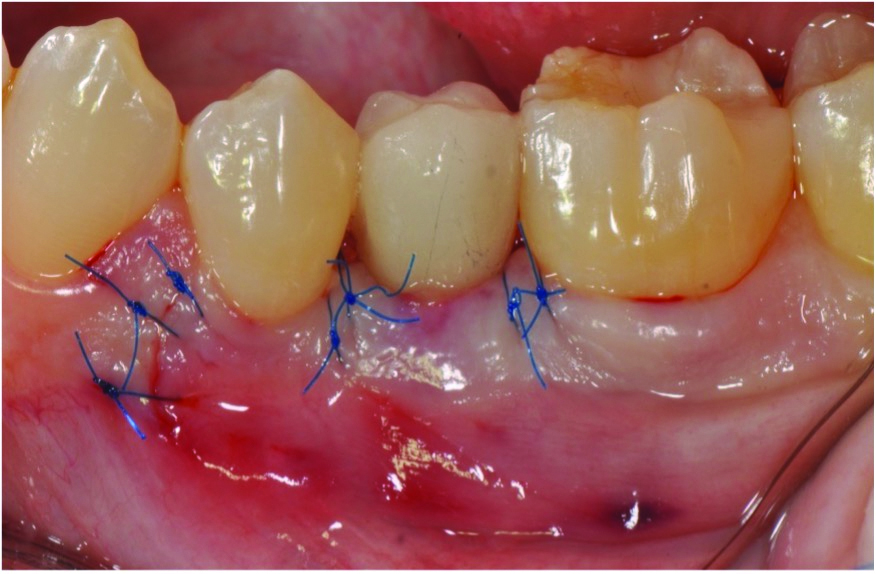

Curettes with small tips were used with ultrasonics to thoroughly clean the intrabony defect while not touching the implant surface (Figure 3 and Figure 4). The surface valleys and threads were carefully cleaned using an air polisher (sodium bicarbonate) for 1 minute, followed by sterile water irrigation of the site for 1 minute. After air drying, EDTA was applied for 1 minute, followed by sterile water rinse for 1 minute, with the previous steps repeated. The FDBA bone graft was soaked in sterile water, dried with a 2 x 2 gauze, and soaked in rhPDGF-BB (Figure 5).51 The bone graft was firmly packed into the defect with slight overpacking above the crest (Figure 6). A collagen membrane was divided in half and soaked in rhPDGF-BB. The collagen membranes were then adapted buccally and lingually with slight overlapping interproximally for graft containment (Figure 7). The flaps were passively positioned coronally and interproximally using nonresorbable 6-0 polypropylene sutures (Figure 8).

Fig 8. Flaps were sutured using nonresorbable 6-0 polypropylene after coronal positioning.

Figure 8